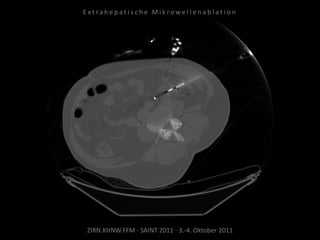

Patient: Weiblich, 82 Jahre

Diagnose: Z.n. Nieren-Ca rechts,

ausgedehnte retroperitoneale

Lymphknotenmetastasen links mit

Verdrängung der linken Niere.

Situation:

Z.n. Nephrektomie rechts, nun

Verlagerung des linken Nierenstiels

durch retroperitoneale Metastasen und

hierdurch Gefährdung der verbliebenen

Niere.

Bildgebung vor MWA:

CT 17.02.2010